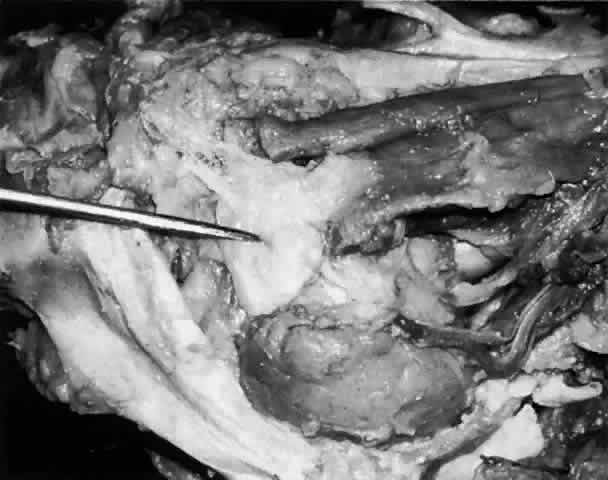

Each lobe of the lacrimal gland is separated into numerous lobules by interlobular fibrovascular connective tissue (Fig. 11). Each lobule, as seen by light microscopy, is composed of two units (Fig. 12): (1) the acinar unit (or secretory unit); and (2) the ductal system. The acinar units are further separated by intralobular fibrovascular connective tissue.

Fig. 11. Lacrimal gland architecture. Each lobe of the lacrimal gland is separated into numerous lobules by interlobular fibrovascular connective tissue. (H & E, original magnification × 5; Courtesy of Ralph Eagle, MD, Philadelphia, PA)

Fig. 12. Lacrimal gland. Each lobule is composed of acinar secretory units (above) and a ductal system. An interlobular duct is seen (lower right). (H & E, original magnification × 25; Courtesy of Ralph Eagle, MD, Philadelphia, PA)